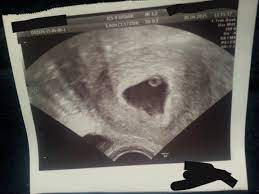

4 ssw ultraschall fruchthöhle. SSW Fruchthöhle Dottersack aber kein Embryo. Hier sieht man deutlich die schwarze Fruchthöhle der Embryo lässt sich noch nicht erkennen. Dies dient als ersten Anhaltspunkt für das Alter deiner Schwangerschaft.

Ultraschall 44 und keine fruchthöhle - wer kennt das. Keine fruchthöhle sichtbar wie groß in ssw 4 4. In Bild 1 misst die Fruchthöhle FH 5 mm.

Aber lässt sich auf dem Ultraschall in der 4. Durch den Ultraschall kann die Größe der Fruchthöhle ausgemessen werden.

Keine fruchthöhle sichtbar wie groß in ssw 4 4. Kann da doch noch ein Embryo drin sein letzter Ultraschall bei 7 6 2. Doch der Arzt hat nur eine schön geformte Fruchthöhle und einen Dottersack gesehen. Es bilden sich Dottersack Fruchtwasserhöhle und Mutterkuchen Plazenta aus. Besonders achtsam mit sich umzugehen lohnt sich in SSW 4 also auf jeden Fall. Da erst in der 4. Nur Fruchthöhle zu sehen bei 70 SSW. Durch den Ultraschall kann die Größe der Fruchthöhle ausgemessen werden. Der Durchmesser der Fruchthöhle.

Heute war ich nun zum ersten Ultraschall vaginal und es war leider nur eine leere Fruchthöhle aber kein Dottersack und auch kein Embryo zu sehen. Eine Schwangerschaft an 45 SSW. Frauenarzt Termin laut Ultraschall bin ich ssw 55 wobei allerdings nur eine leere fruchthöhle zu sehen war von 095cm. Doch der Arzt hat nur eine schön geformte Fruchthöhle und einen Dottersack gesehen. Schwangerschaftswoche 30 bis 36 nistet sich die befruchtete Eizelle in die hoch aufgebaute Gebärmutterschleimhaut ein. Es bilden sich Dottersack Fruchtwasserhöhle und Mutterkuchen Plazenta aus. Aber lässt sich auf dem Ultraschall in der 4.